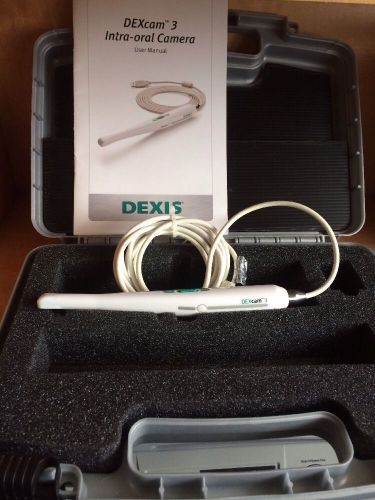

Dexis DEXcam 3 Diagnostic Imaging USB Dental Intraoral Camera-Works great!!